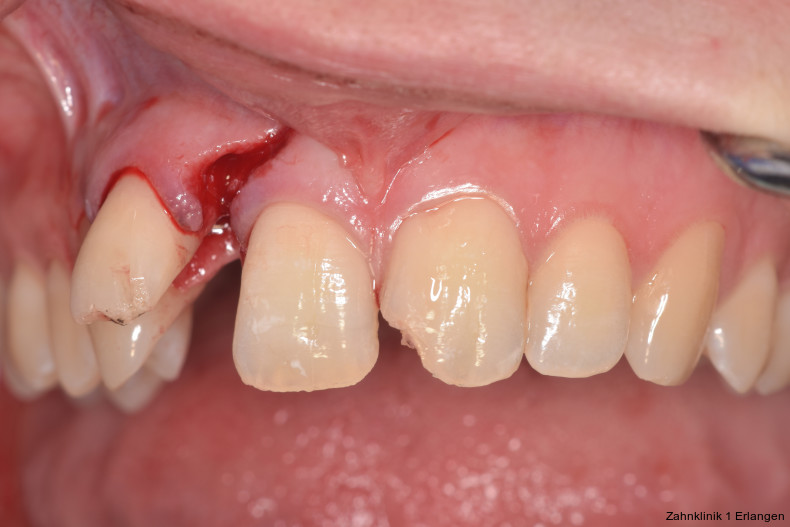

Zu den Zahnfrakturen mit Pulpabeteiligung gehören die in das Dentin reichende unkomplizierte Kronenfraktur sowie die komplizierte Kronenfraktur mit Pulpaexposition. Rein schmelzbegrenzte Frakturen sind hinsichtlich des Pulpastatus als unkritisch einzuschätzen.1 Dislokationsverletzungen betreffen die Pulpa insofern, als das Gefäß-Nerv-Bündel je nach Ausprägung der Positionsveränderung gestaucht, gedehnt oder abgerissen sein kann. Bei Zähnen mit abgeschlossenem Wurzelwachstum geht man davon aus, dass spätestens ab einer Dislokation von 2 mm die Pulpa abgerissen wurde, was die zeitnahe Einleitung der Wurzelkanalbehandlung notwendig macht.2, 3 Bei geringer ausgeprägter Dislokation kommt den Nachkontrollen eine wesentliche Rolle zu, bei denen jeweils dem Pulpastatus besonderes Augenmerk zukommen sollte, um eine Pulpanekrose frühzeitig zu detektieren.

Zu den wesentlichen diagnostischen Verfahren, die zur Erfassung des Pulpastatus herangezogen werden, gehören neben der Inspektion und der röntgenologischen Bildgebung die Sensibilitätsprüfung sowie der Perkussionstest. Der Inspektion kommt insbesondere bei der Erstbehandlung eine wesentliche Rolle zu. Hierbei wird abgeklärt, ob es sich bei Zahnfrakturen um eine schmelzbegrenzte Verletzung handelt, ob das Dentin mitbetroffen und ob zusätzlich die Pulpa exponiert ist. Bei Dislokationsverletzungen wird das Ausmaß der Positionsveränderung erfasst und ob zusätzliche Gewebe wie Knochenstrukturen oder umliegende Weichgewebe betroffen sind. Auch können Farbveränderungen des Zahnes erfasst werden. Die Röntgendiagnostik zum Zeitpunkt des Unfalles gibt Aufschluss über die Größe des Pulpenkavums und das Lumen des Wurzelkanals, den Stand des Wurzelwachstums und die periapikalen Verhältnisse. Des Weiteren finden sich möglicherweise Hinweise auf eine Wurzelfraktur.

Versorgung von Zahnfrakturen mit Pulpabeteiligung

Unkomplizierte Kronenfrakturen mit Verlauf im Dentin sind als Wundfläche einzuschätzen, bei der es bei anhaltender Exposition zum Mundhöhlenmilieu zur Infektion der Pulpa über freiliegende Dentintubuli kommen kann. Somit ist ein wesentlicher Grundsatz der Erstversorgung, die Dentinwunde abzudecken,3, 8 vor allem bei jungen Patienten mit großlumigen Dentintubuli. Die Abdeckung kann im Zuge der Notfallbehandlung mit Glasionomerzement erfolgen oder mittels fließfähigem Komposit unter Verwendung eines Dentinadhäsivs. Hilfreich im Hinblick auf die spätere Wiederentfernung ist dabei die Verwendung eines falschfarbenen oder opaken Materials, um die provisorische Abdeckung bei der definitiven Versorgung gezielt wieder entfernen zu können. Bei pulpanahen Verletzungen empfiehlt sich die Abdeckung mit einem biokompatiblen Material wie hydraulischem Kalziumsilikatzement oder Kalziumhydroxid im Sinne einer indirekten Überkappung.3 Betroffene Zähne können durch Wiederbefestigung des Zahnfragmentes9 oder mit Komposit restauriert werden, dies kann jedoch auch erst bei der Weiterbehandlung erfolgen.

Bei Pulpaexposition ist die oberste Prämisse der Erhalt der Vitalität des Zahnes. Vor allem bei jungen Patienten und bei nicht abgeschlossenem Wurzelwachstum, aber auch bei erwachsenen Patienten ist die Vitalerhaltung die Methode der Wahl. Dabei spielen die Dauer und die Größe der Exposition keine wesentliche Rolle.10 Die oberste Gewebeschicht sollte zunächst im Sinne einer Mikropulpotomie angefrischt werden, was mit einem Diamantschleifer unter Wasserkühlung durchgeführt werden kann. Nach Blutstillung, zu der Natriumhypochlorit tropfenweise appliziert werden kann, wird das Sistieren der Blutung kontrolliert. Ist dies verifiziert, wird ein biokompatibles Material in direktem Kontakt mit dem Gewebe aufgebracht und der Zahn anschließend adhäsiv verschlossen.10 Dauert die Blutung an, beispielsweise weil der Unfall bereits mehr als 24 Stunden zurückliegt, kann tiefer pulpotomiert werden. Da eine traumatisch geschädigte Pulpa in der Regel vor dem Unfall gesund war, ist die Heilungskapazität meist sehr gut.11 Auch bei bestehender Exposition zur Mundhöhle hin über einen Zeitraum von Tagen kann die Pulpotomie noch hohe Erfolgsraten erzielen.